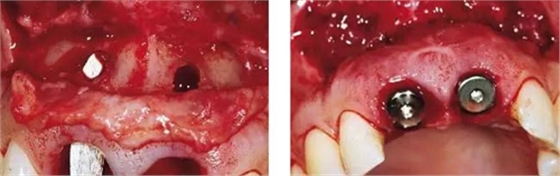

圖6、從磨牙后區(qū)用環(huán)形鉆獲取自體骨,并將其放置在種植體的表面。Geistlich Bio-Oss®骨顆?;旌涎悍胖迷谧泽w骨的外側,防止自體骨的早期吸收。植骨可以穩(wěn)定軟組織外形。

圖7、植骨區(qū)外覆蓋Geistlich Bio-Gide®雙層膠原膜,使得植骨區(qū)更為穩(wěn)定。

圖8、植入2顆Camlog平行壁螺紋種植體,扭矩達35Ncm。安放兩個粗直徑的愈合帽,防止軟組織退縮和凹陷。

圖9、頰側骨壁用自體骨覆蓋,Geistlich Bio-Oss®覆蓋在自體骨的外側,Geistlich Bio-Oss®同樣也要放置在基臺與牙齦之間,以支撐牙齦的外形。

圖10、為了避免對植骨區(qū)的干擾,外側覆蓋Geistlich Bio-Gide®膠原膜。